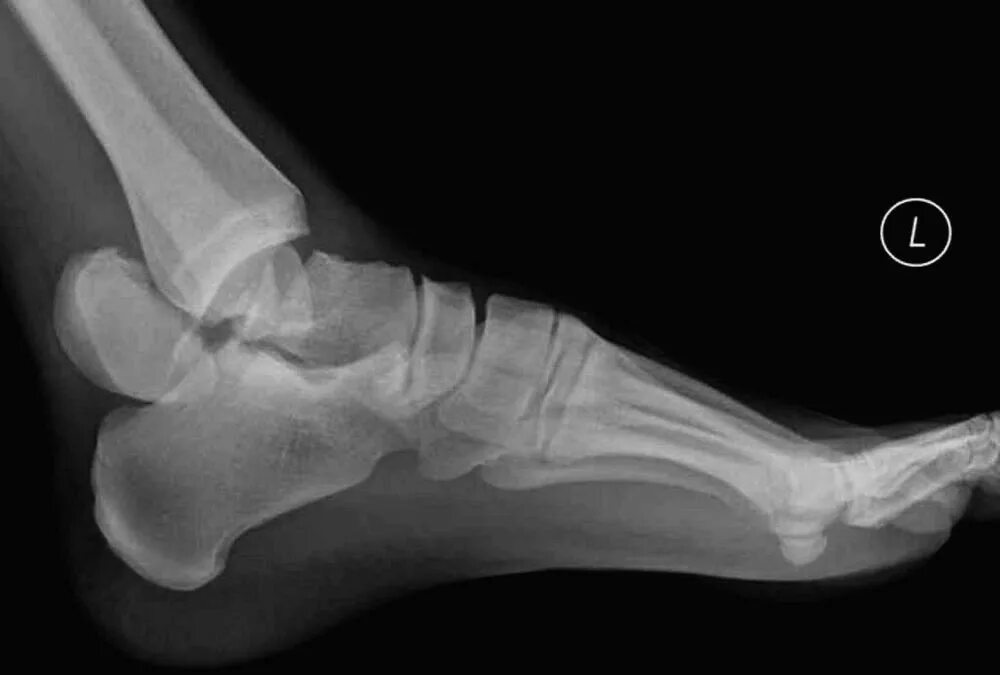

Перелом заднего